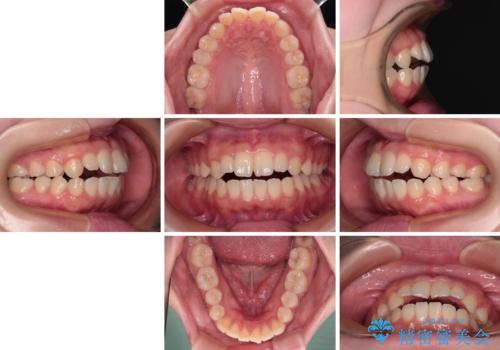

- 前歯が開いて飛び出していることを気にして来院された患者様です。

舌の突出癖により上下前歯は接触できず、更には前方に押し出されて出っ歯になっている状態でした。

上下左右の第一小臼歯4本を抜歯し、ワイヤー装置での抜歯矯正を行っていくのですが、原因である舌の突出癖を改善しないことには治療がうまく進められないため、舌のトレーニングを徹底するよう指導していくこととしました。